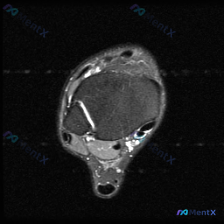

看到这张踝关节MRI,问题问有什么异常,很多人第一反应就是看到软组织积液,但其实背后藏着更关键的问题,我整理一下完整的分析思路给大家。 病例影像基础信息 这是一张踝关节MRI T2序列轴位影像,我们先把所有能看到的征象理清楚: 1. 骨骼结构:影像中心是距骨横截面,皮质骨低信号、骨髓中等信号,骨质轮...

看到这个踝关节MRI的病例,整理了完整的影像资料和分析思路,和大家分享讨论。 病例影像基础信息 这是踝关节MRI T2加权轴位图像,扫描层面为踝关节远端,可见距骨体及周围软组织结构,图像对比度满足观察要求,T2加权像液体呈高信号。 核心影像发现 1. 骨结构:距骨及周围骨性结构骨髓无异常高信号,骨皮...

刚看到这份踝关节MRI读片需求,整理了完整的观察和分析思路分享给大家。 病例基本影像信息 本次读片基于踝关节MRI-T2序列轴位图像,扫描层面为踝关节远端轴位,可清晰辨认胫骨、腓骨、距骨以及后方跟腱等正常解剖结构。T2序列对液体和水肿敏感,正常肌腱韧带应为低信号(黑色),液体/水肿为高信号(白色)。...

刚整理完一份踝关节MRI的读片分析,关于软组织积液的鉴别思路挺典型,分享给大家一起讨论。 病例影像基本信息 这是一份踝关节MRI T2序列轴位影像,扫描层面为距骨体水平,显示踝关节及周围软组织结构: 1. 骨骼表现:距骨及周围骨性结构骨皮质完整,骨髓信号无局灶异常高信号,排除明显骨挫伤、骨折或骨髓水...

刚看到这张踝关节T2轴位MRI,我整理一下影像表现和分析思路,跟大家讨论一下。 病例影像基本信息 这是踝关节轴位T2加权MRI,液体呈高信号(亮白色),骨皮质、肌腱韧带呈低信号(黑色)。 先看基础结构: - 骨性结构:胫骨、腓骨、距骨截面可见,骨髓信号均匀,没有明显骨质破坏或异常骨髓水肿 - 肌腱结...

最近看到一份踝关节MRI的影像分析,整理了整个诊断思路分享给大家,一起讨论下。 病例影像基本信息 这是踝关节轴位T2加权MRI扫描,核心发现整理如下: 1. 骨骼结构:胫骨、腓骨、距骨骨皮质完整,没有骨折线,骨髓信号均匀,无明显弥漫性骨髓水肿 2. 肌腱韧带:内外侧肌腱、跟腱走行正常,信号均匀,无腱...

今天整理了一份踝关节MRI的读片分析,核心问题是影像发现「软组织积液」该怎么判断,分享出来大家一起讨论。 病例影像基础信息 这是一份踝关节轴位T2加权MRI(T2WI)的读片报告,核心信息整理如下: 1. 骨骼结构:胫骨远端、距骨骨髓信号正常,无骨髓水肿、骨质破坏,皮质完整,未见骨折线 2. 关节结...